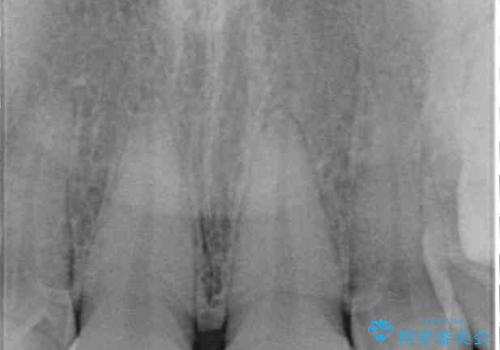

- 大きすぎる上顎前歯と、隙間の空いた下顎歯列を気にして来院された患者様です。

上顎前歯にはセラミッククラウンが装着されており、顔や他の歯と比較して幅の大きい状態でした。

下顎前歯は空隙歯列弓であったので、アンカースクリューとワイヤー装置を用いてスペースを閉じていくこととし、上顎前歯は矯正治療用の仮歯に置き換えた上で、仮歯の大きさを削って小さくしながら、上下前歯部の部分矯正を行うこととしました。